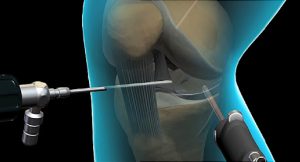

PATELOFEMORAL

S. PATELOFEMORAL